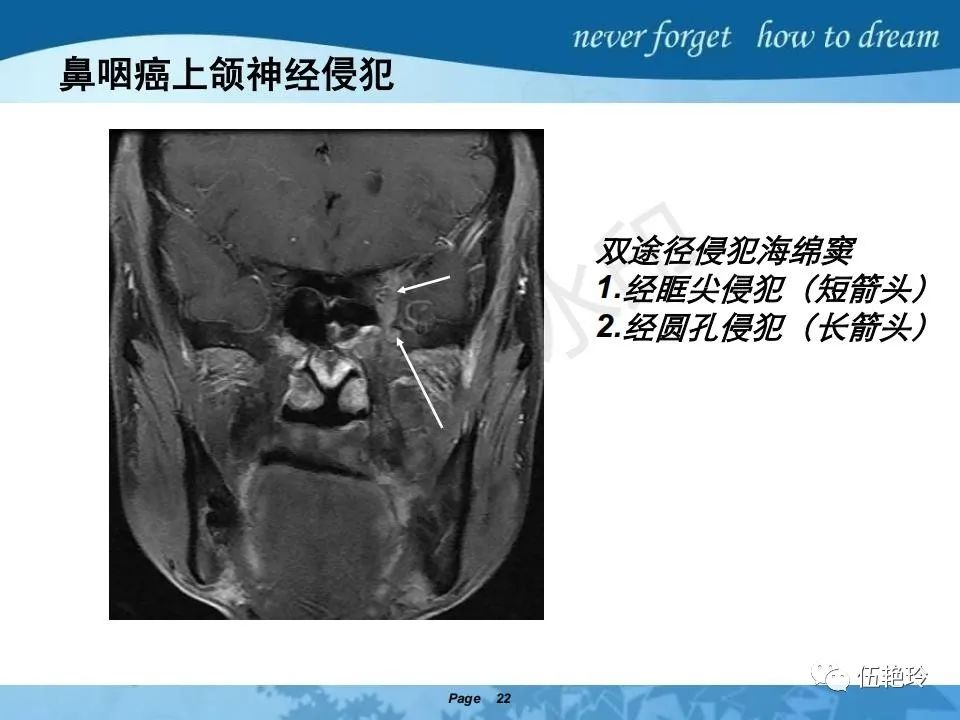

海绵窦区的解剖结构与鼻咽癌侵犯

2.2 鼻咽特有的解剖途径:鼻咽癌原发灶循序进展的总途径:鼻腔(47.8%)→翼腭窝(15.2%)→ 眶下裂(3.2%)→眶尖(1.2%)→海绵窦(0.6%)。

2.31 向上颅内:①鼻咽顶壁→破裂孔(岩尖、斜坡)→蝶窦、海绵窦;②鼻咽顶壁→蝶骨基底部→蝶窦、海绵窦;③鼻咽侧壁→茎突前间隙→蝶骨大翼(卵圆孔)→海绵窦;④鼻咽侧壁→茎突前间隙→翼腭窝→ 颞下窝;⑤鼻咽前壁→鼻腔→翼突、翼腭窝→眶下裂→眶尖→海绵窦;⑥鼻咽前壁→鼻腔→上颌窦、筛窦;